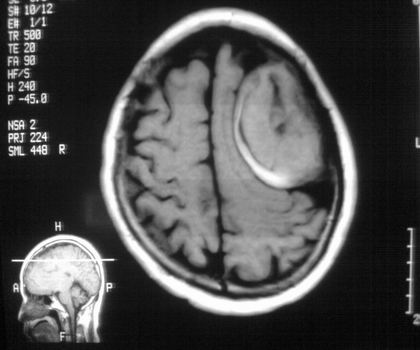

以下是引用影像孺子牛在2008-4-29 21:20:00的发言:[br]首先病变定位在脑外,根据ct密度及mri信号特征考虑慢性硬膜下血肿不连续环形钙化。

以下是引用周战梅在2008-4-29 23:12:00的发言:[br]脑外病变,蛛网膜下腔增宽,囊壁点状、环形钙化,增强扫描呈不均匀环状强化,考虑为囊性脑膜瘤可能性大,慢性脓肿、血肿机化、胆脂瘤不能除外。